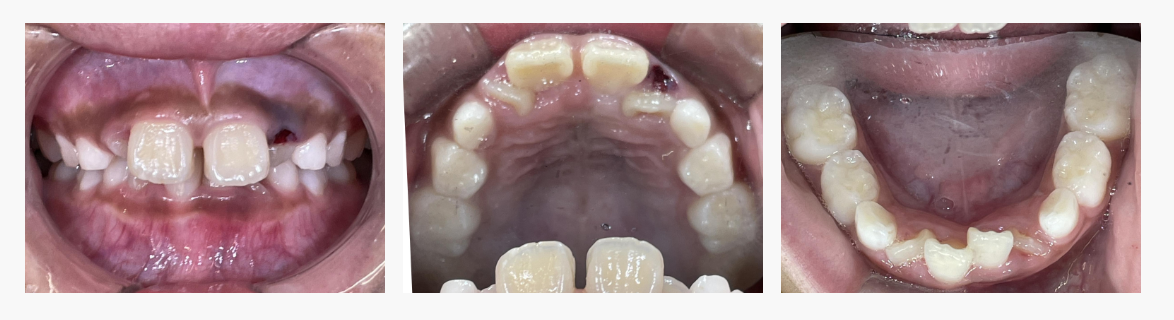

▼ Before(治療前)

初診時の状態

・上顎前歯の前方突出

・前歯部の叢生

・口唇閉鎖不全(安静時に口が閉じにくい)

歯並びだけでなく、口元の筋機能にも影響が出ている状態でした。